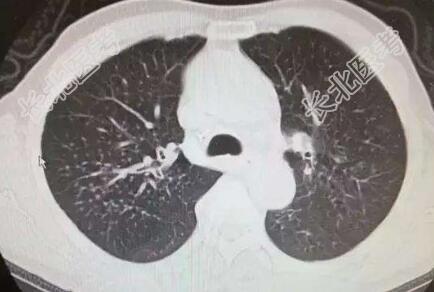

男性,68岁,退休。反复憋喘20余年,头晕下肢水肿2年,加重10天。现病史:患者既往20余年前开始出现咳嗽咳痰,胸闷气喘,好发于秋冬季节,易迁延不愈,曾在多家医院就诊,诊断为\"慢阻肺、心功能不全\",予以对症支持治疗好转出院。近2年来自感憋喘发作较前进展,并出现阵发性头晕下肢水肿,间断服药及在当地诊所输液治疗(利尿剂、抗感染、解痉平喘等),仍时有发作,近10天来受凉后再次出现胸闷气短心慌,进食及活动后明显,有咳嗽少量咳痰,白粘痰量不多,纳差乏力,头晕下肢水肿,在当地诊所输液治疗(抗感染、平喘等)效果一般,今家人为求进一步治疗,特来我院,门诊拟\"慢支\"收入我科,发病以来患者神清精神差,无头晕头痛、咯血胸痛,无偏瘫失语,无恶心呕吐,二便尚正常。既往史:既往脑梗死高血压病10余年,遗留右侧肢体偏瘫,自服药不详。个人史:个人及家族史无特殊查体:T:36.2℃,P:97次/分,R:22次/分,BP:110/70/mmHg。神情精神萎,问答切题,发育正常,体型中等,呼吸稍促,推入病房,自主体位,查体尚合作,全身皮肤黏膜无黄染,浅表淋巴结未及肿大;颈静脉无怒张,头颅无畸形,双瞳孔等大等圆,直径3.0mm,对光反射灵敏;唇无紫绀,伸舌居中;颈软无抵抗,气管居中,甲状腺不大。胸廓呈桶状,肋间隙增宽,两肺呼吸音粗,可及哮鸣音及少量湿啰音,心率97次/分,律齐,各瓣膜听诊区未及明显杂音。腹平软,无包块,无压痛反跳痛,肝脾未及,肠鸣音正常无亢进,移动性浊音阴性。脊柱四肢无畸形,右侧上肢肌力3+,下肢3-,生理反射存在,双下肢水肿,双侧巴氏征(+)。辅助检查:心电图:窦性心律,肺型P波,T波改变;心脏彩超:主动脉瓣退变伴少量反流,左室舒张功能减退;颅脑+胸部+颈部CT:双侧基底节区、丘脑、放射冠多发新陈梗塞灶,老年性脑改变,C3-4C4-5椎间盘突出,C6椎体后缘增生,右上肺结节影。